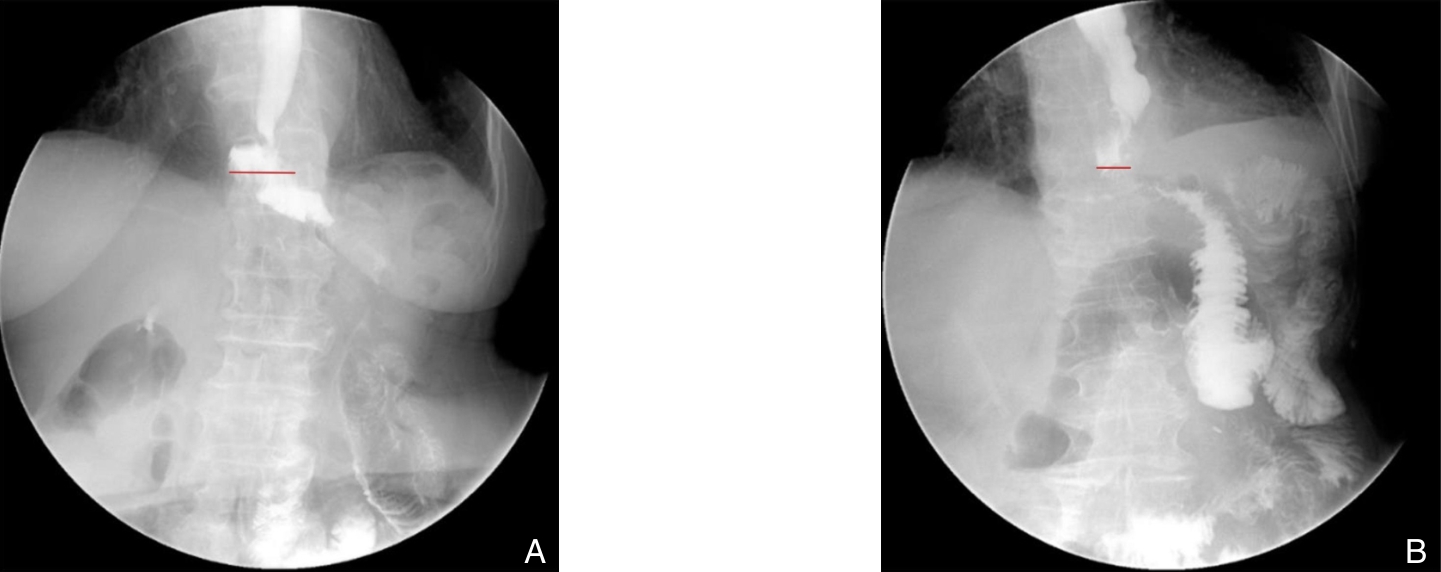

背景与目的 Hem-o-lok夹广泛应用于腹腔镜胆囊切除术(LC)中的胆囊管及血管闭合,但其术后移位虽罕见,却可进入胆总管形成异物,影像学表现易误诊为胆总管结石,增加诊断与治疗难度。针对该远期并发症的识别与处理,临床认知仍有不足。本文通过分析1例相关病例并结合文献复习,总结其临床特征及诊治要点。方法 回顾性分析中国人民解放军空军军医大学第二附属医院普通外科2025年10月收治的1例29岁女性患者的临床资料。患者4年前行LC,本次因体检发现“胆总管结石”1年余入院,术前影像学提示胆总管多发充盈缺损。患者拒绝内镜下逆行胰胆管造影治疗,遂行腹腔镜胆总管探查术(LCBDE),术中确诊为Hem-o-lok夹移位。分析其诊疗过程、影像学特征及术中所见,并结合文献进行讨论。结果 术前影像学提示胆总管多发结石。LCBDE术中经胆道镜探查,于胆总管中下段取出3枚移位的Hem-o-lok夹,周围未见胆色素结石,确诊为“胆总管异物(Hem-o-lok夹)”。术后置T管引流,恢复顺利出院。术后2个月T管窦道造影示胆总管通畅,无残留异物或结石,顺利拔管。结论 Hem-o-lok夹移位是LC术后一种罕见的远期并发症,影像学易误诊为胆总管结石。对有相关手术史的患者,应将其纳入鉴别诊断。LCBDE是确诊及处理该并发症的有效方式。规范术中操作及合理选择闭合方式,并加强术后随访,有助于降低此类并发症风险。